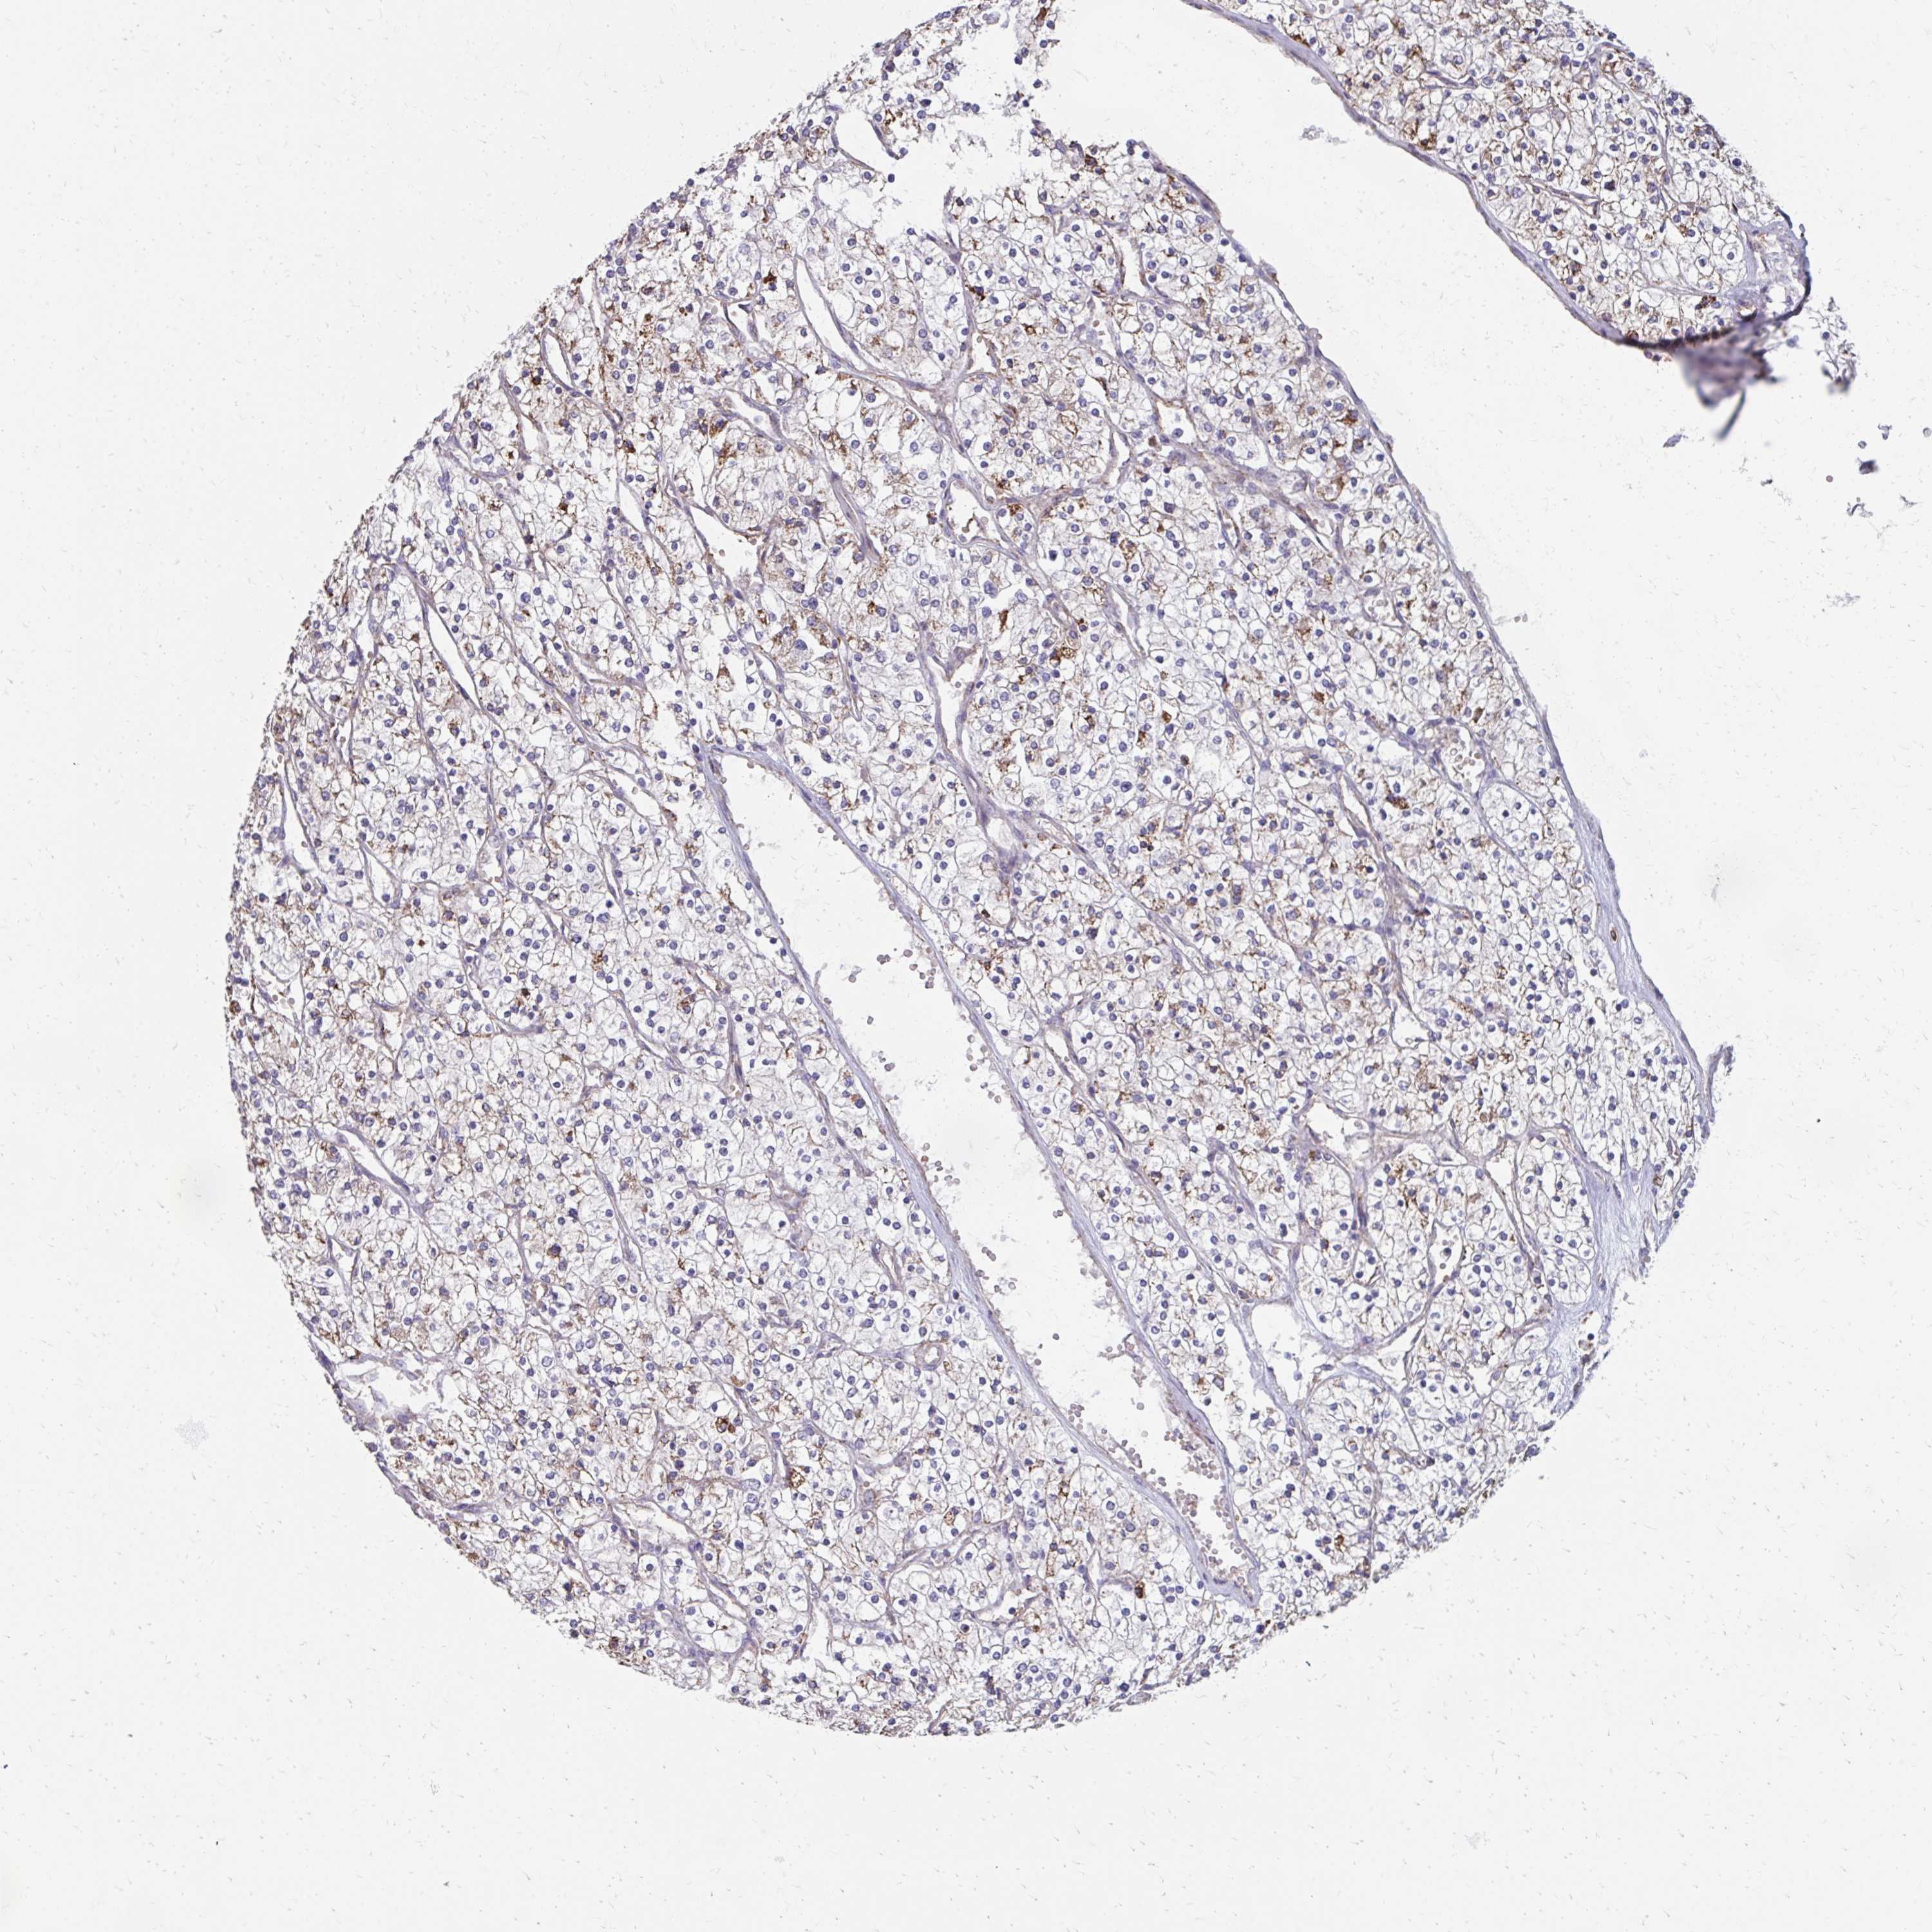

CANCER RENAL CANCER Show tissue menu

Renal cancer

Kidney renal papillary cell carcinoma